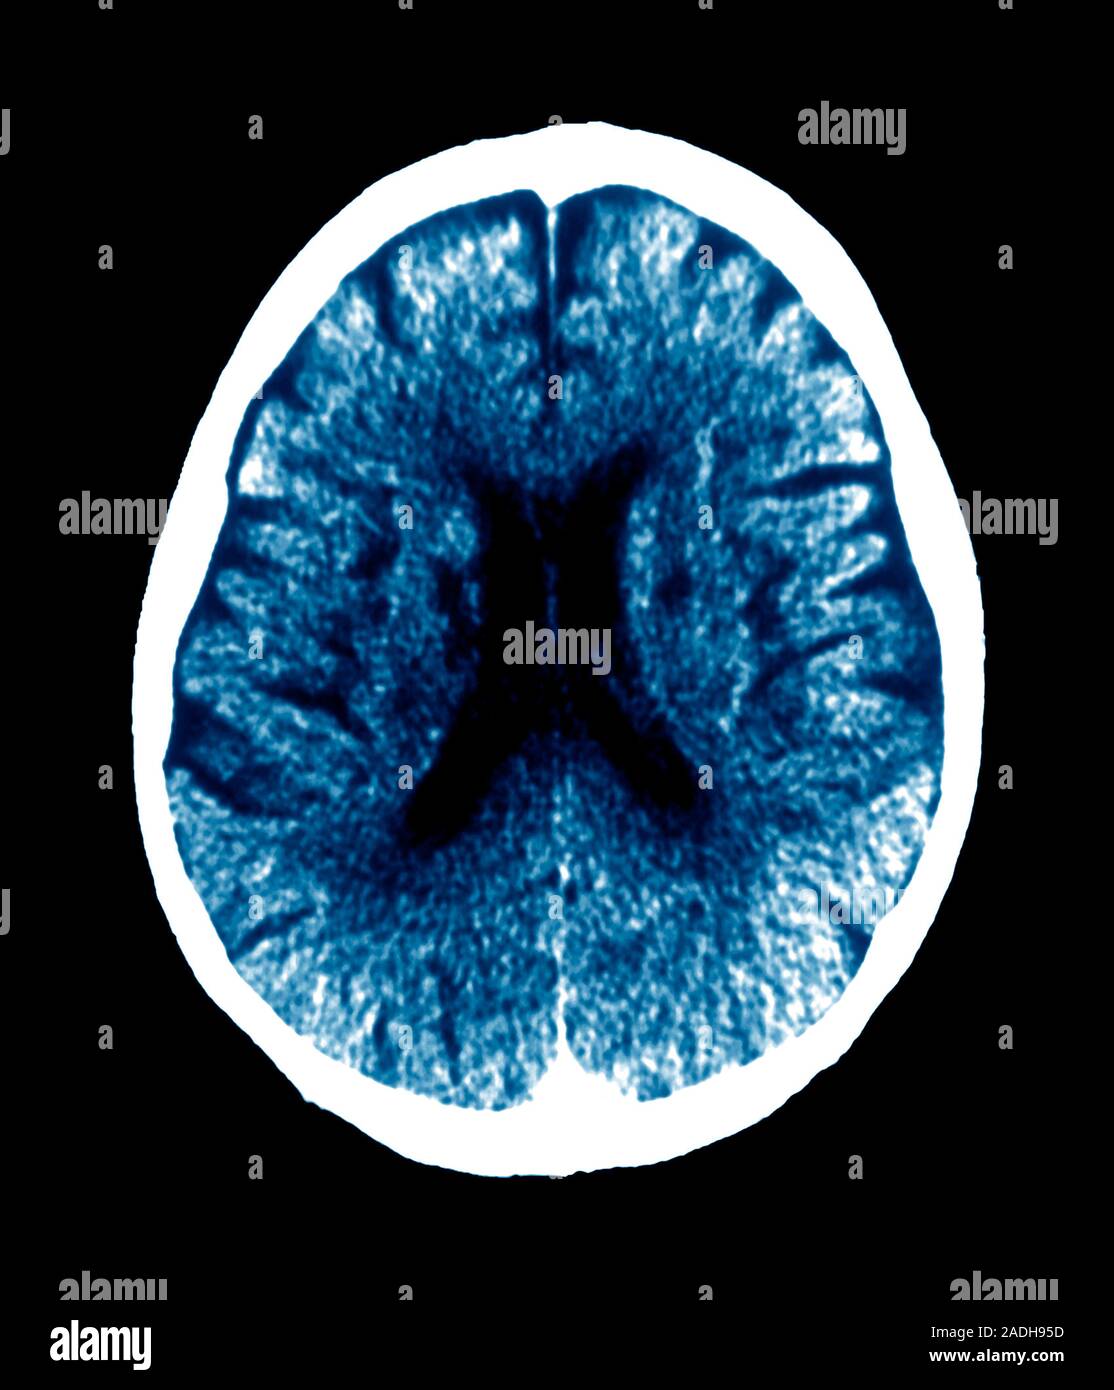

La enfermedad de Binswanger, también llamada encefalopatía subcortical o demencia vascular subcortical, es un tipo de demencia poco habitual que se caracteriza por la afectación de los pequeños vasos sanguíneos situados en la región subcortical del cerebro (demencia vascular)[1] y la aparición en las pruebas de imagen como la resonancia magnética nuclear de rarefacción de la sustancia blanca (leucoaraiosis) y múltiples infartos lacunares subcorticales.[2][3] Los primeros síntomas suelen aparecer entre los 54 y 64 años y consisten generalmente en deterioro cognitivo, más adelante es habitual que se produzca accidente cerebrovascular.[4][5]